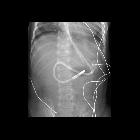

Toddler after

feeding tube placement. CXR AP shows a feeding tube which courses into the stomach and then loops back upon itself and reenters the esophagus and whose tip lies at the level of C6.The diagnosis was feeding tube malfunction with malposition of the feeding tube tip in the cervical esophagus.